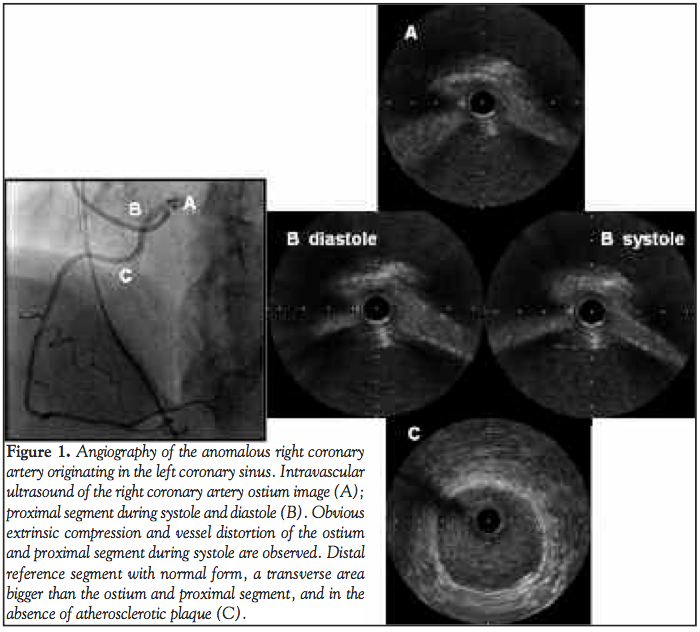

Case Report 1. The first patient was a 69-year-old male who was seen at the emergency room for angina chest pain that lasted 15 minutes. The electrocardiogram showed a T-wave inversion in the inferior wall. There was no increase in myocardial injury markers. The patient underwent stress myocardial scintigraphy, which showed reversible perfusion deficit in the inferior wall. The anomalous origin of the RCA, arising from the left coronary sinus, was observed by angiography. A constriction of the ostium and the proximal segment of the artery were also observed. The left coronary artery was normal. There was no atherosclerosis by coronary angiography. IVUS confirmed a significant stenosis in the medial segment, with a luminal area of 4.34 mm2 and without the presence of atherosclerotic plaques. There was no observed asymmetry of the coronary ostium (Figure 1, Table 1), and significant atherosclerosis was not identified. The patient underwent coronary artery bypass surgery involving an implantation of the right internal thoracic artery to the RCA and proximal coronary artery ligation. The patient recovered favorably and was discharged in good clinical condition and without angina on the seventh postoperative day.

Discussion. For these 3 patients, the main findings from the IVUS were the absence of significant atherosclerotic disease, a marked reduction in the luminal area at systole, and an asymmetry of the ostium lumen and the proximal segment of the RCA (Table 1). The pharmacological stress test showed a reduction of the coronary lumen that was associated with the development of symptoms.